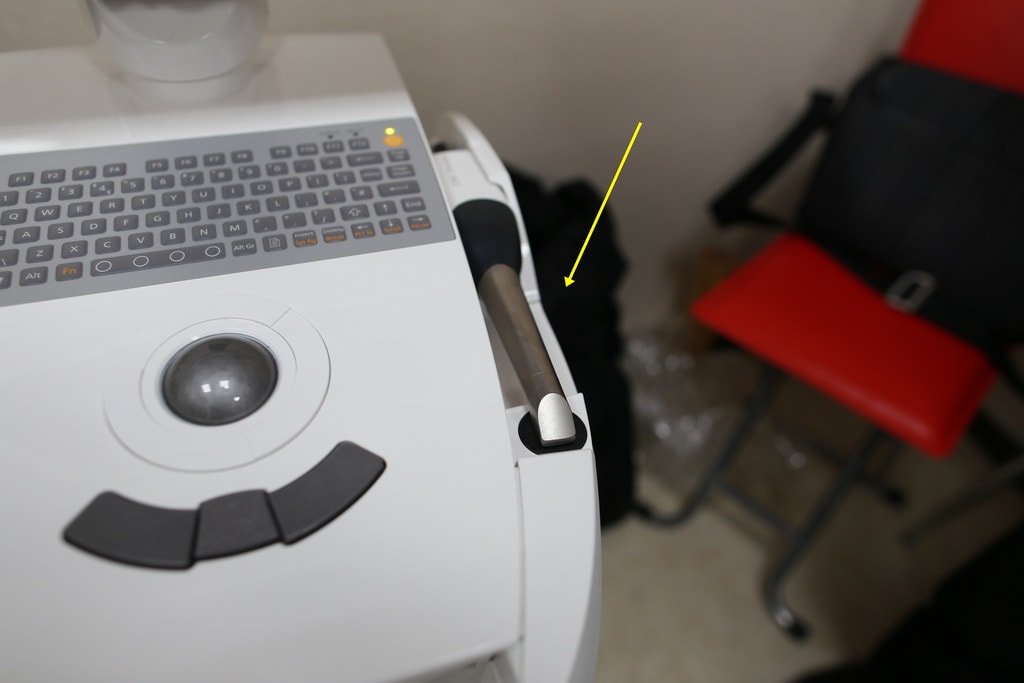

不得不說悅庭牙醫的所有醫療器材真的很棒,這台是CEREC 3D齒雕數位取像儀是最新引進的

這台最主要是植牙植進去人工牙根後需至少三個月後才可以做假牙,這時候就會使用這台機器

現場院長也有提供當初CEREC 3D齒雕數位取像儀在美國發表會的影片

CEREC 3D齒雕數位取像儀是臨床使用的全瓷牙高科技設備,擁有自動電腦運算科技、細緻的光學影像技術、精確的研磨製造程序

能在一個診次完成美觀的全瓷修復體;病患不需戴上臨時牙套,不需多次約診與等待一週,當天立即完成高品質的全瓷修復治療

輕巧的CEREC 3D鏡頭,可於病患口內拍攝立體影像,立即取得精確的口內數位模型

進行後續的軟體設計,杜絕傳統翻模誤差,大幅節省臨床時間,提升修復體密合度

CEREC 3D軟體有非常方便的使用者介面,使用者透過3D鏡頭對治療區域取像後,軟體能夠立即將影像轉換成3D無死角的立體虛擬模型

清楚呈現病患口內真實修型的狀況,再運用軟體輕鬆快速的完成修復體的設計

在軟體上就能預先看到咬合的情況直接調整,能夠精準控制咬合高度

且咬點位置都能夠利用CEREC 3D 強大的軟體來控制,大幅降低臨床調整時間

數位印模能提供比傳統印模更精密的數位模型,杜絕傳統印模經常發生的許多誤差

再來搭配這台搭配高精密且立即在短時間內的研磨機

德國CEREC 3D齒雕機採用精密的研磨系統,全自動化的研磨控制

提供快速與精確的研磨成果,平均一個修復體只需10分鐘即可完成

機器上也有製作時間顯示喔

短短時間內就製作完成啦!!